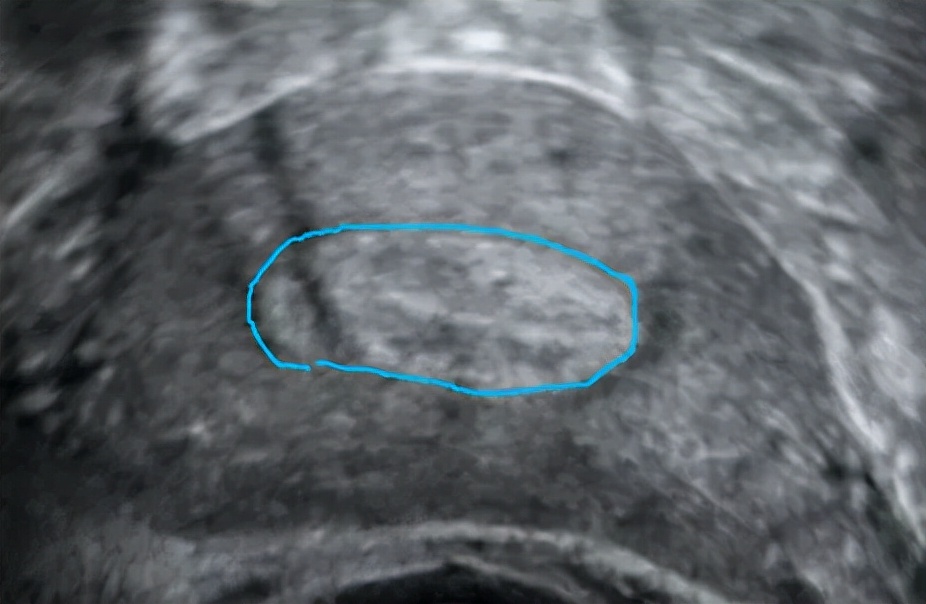

正常内膜长这样

画蓝线的地方是正常内膜的范围